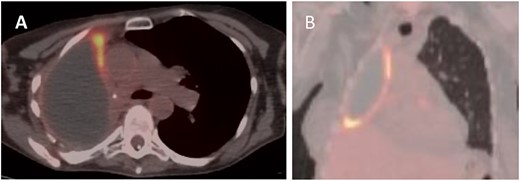

A 60-year-old woman with stage IIIA right lung adenocarcinoma underwent neoadjuvant chemoradiation followed by pneumonectomy. Nine years later, surveillance CT/PET scans revealed new right pleural thickening and nodular avidity with concerns for malignant recurrence (Figs 1 and 2). Her only symptom was chronic chest pain attributed to post-thoracotomy syndrome. She had no respiratory symptoms. She underwent a bronchoscopy which showed an intact right mainstem bronchial stump without signs of tumor or fistula. Upon entry into the pleural cavity during video-assisted thoracoscopic surgery for pleural biopsy (VATS), 10 mL of white, non-odorous fluid was drained. There was no intra-operative suggestion of cancer recurrence. Pathology of the pleural biopsy showed acute inflammation with underlying chronic pleuritis and no tumor. Pleural cultures were positive for N. nova, consistent with PPE (Fig. 3). She then started on intravenous trimethoprim-sulfamethoxazole and amikacin. Brain MRI and blood cultures were negative for disseminated nocardiosis. She was planned for washout and muscle transposition to fill the pneumonectomy space, but clinically deteriorated after aspiration pneumonia and cardiogenic pulmonary edema. She elected for comfort measures and expired shortly afterwards.

PET (A) axial and (B) coronal views showing increased FDG uptake (max SUV 9.5) along the anteromedial and inferior aspects of the right lung pleura.